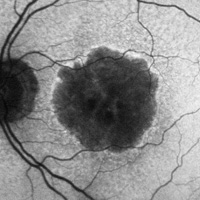

ImageWet AMD

- Mako Study, phase 3 study of the Efficacy and safety of Squalamine Lactate Ophthalmic Solution 0.2% administered twice daily in subjects with neovascular age-related macular degeneration